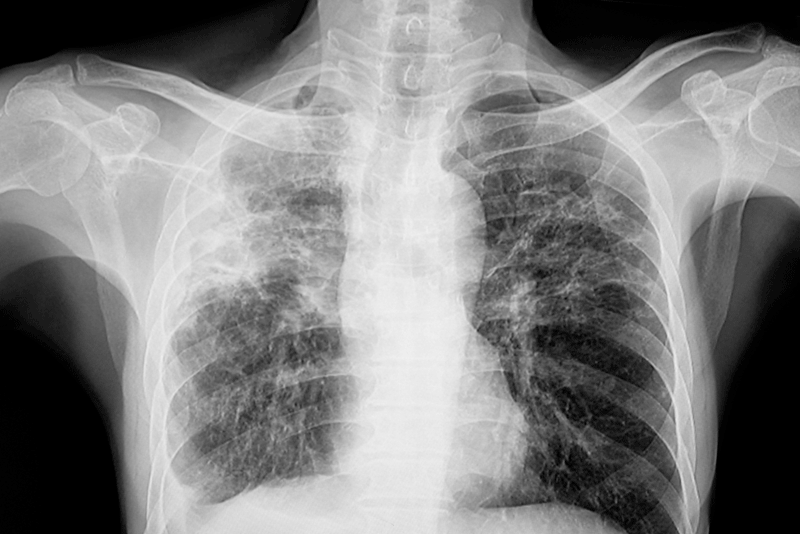

Main image: Dr Lo advises individuals with a cough lasting more than two weeks to seek prompt medical attention, as it may be a sign of tuberculosis (TB).

Dr Lo emphasised that one of the earliest and most common signs of active pulmonary TB is a persistent cough lasting more than two weeks. Other symptoms include night sweats, low-grade fever, fatigue, unintentional weight loss, and in more advanced cases, coughing up blood-stained sputum or chest pain.